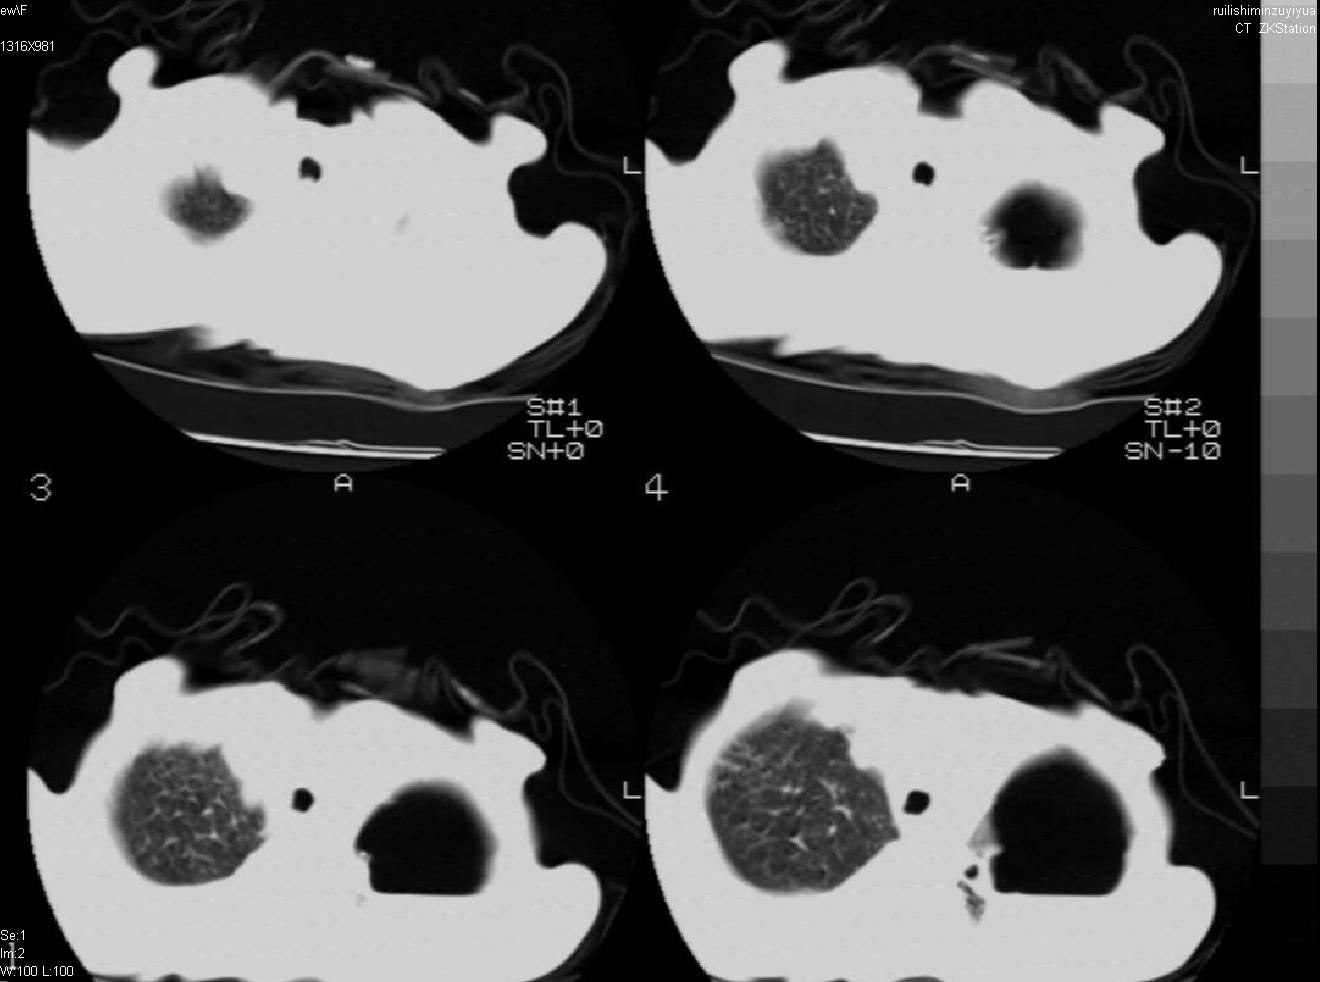

以下是引用天南地北在2007-6-11 23:32:00的发言:[br]1:左侧肺毁损(结核性)伴感染(多发空洞伴液平面)。[br]2:右肺继发型肺结核。

以下是引用avril在2007-6-12 1:17:00的发言:[br]1、左肺毁损。[br]2、左肺多发肺大泡伴自发性气液胸形成。[br]3、右肺继发型结核。